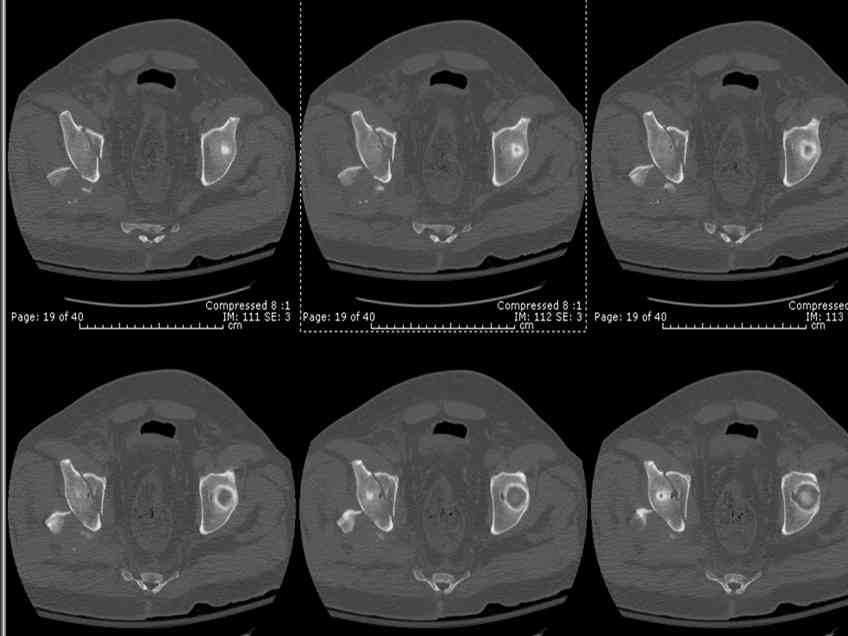

Stabilize anterior column with fluoroscopically guided screw across this end of the transverse fx - As usual, after your reduction of the femoral head, the transverse fx became minimally displaced - slightly gapped without stepoff. I usually (reduce &) stabilize the medial side of the posterior column (transverse fx) with a short plate - before placing the anterior screw unless the transverse fx is undisplaced.

Biggest problem appears to be impaction & comminution of the posterior wall fx site - you've left out some CT cuts. This is not just fragments in joint. It may leave a deficient area, &/or block satisfactory posterior wall reduction.

May need to bone graft elevated articular fragments. Lag screws & more lateral contoured plate to buttress PW. Make sure this reduction is

anatomical.